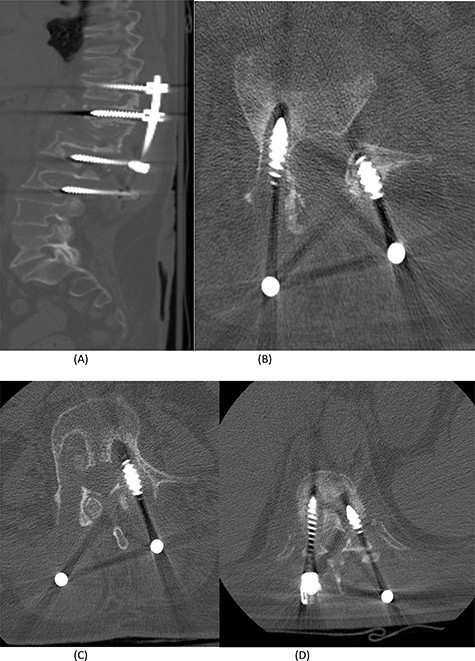

(A) AP lumbar spine X-ray demonstrating the bridging technique. (B) Lateral spine X-ray showing the bridging technique sparing the infected area.

The bridging technique was used to achieve relative stability through posterior fixation until the anti-TB medications cleared the vertebral infection and allowed re-ossification of the destructed levels (T11–L3) to occur. An open biopsy was done intraoperatively to reconfirm the diagnosis of spinal TB. The patient started mobilizing early postoperatively and continued to take the anti-TB medications for 18 months (Fig. 4).

The success rate of surgical TB management is high and effective according to a study based on data collected from 582 patients throughout 11 years [8]. Our patient presented with a destructive spinal lesion and underwent posterior spinal decompression and instrumentation of T11–L3. Nevertheless, due to severe destruction, loosening and poor bone quality of the levels T11–L3, along with the multiple medical comorbidities, anterior surgical intervention with a thoracoabdominal approach with resection of all the levels involved would associate with major morbidities and complications. To achieve a balanced construct and to have multiple fixation points, which was needed to overcome the poor bone quality, the fixation was done from T5 down to the pelvis (Fig. 4), spanning the destructed area and utilizing the bridging technique with multiple rod constructs across the T11–L3 region.